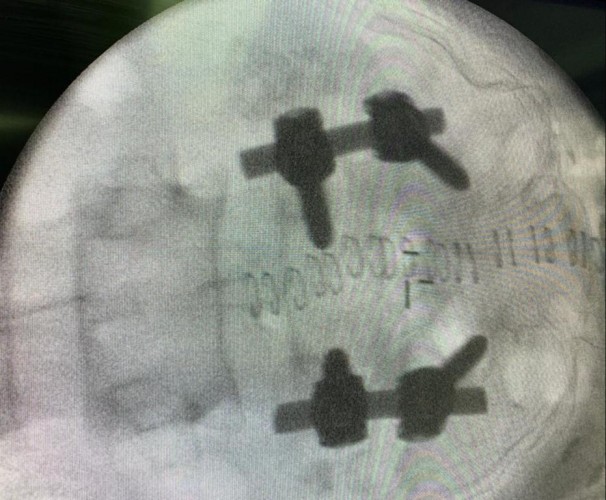

أجريت العملية للمريض حيث تم تثبيت الفقرات المنزلقة بالإضافة الى زرع غضروف قطني بدل الغضروف التالف، تكللت العملية بالنجاح ولله الحمد دون أي مضاعفات بعد أن استمرت ما يقارب 3 ساعات، غادر بعدها المريض المستشفى وهو بصحة جيدة.